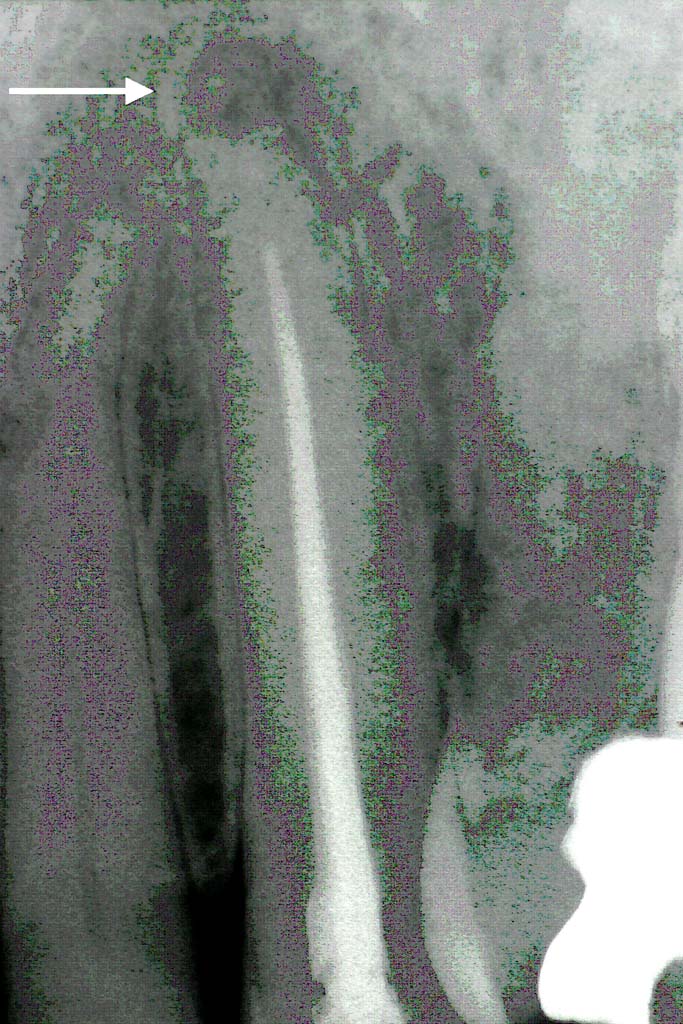

Breitet sich die Entzündung über den Wurzelkanal hinaus an der Wurzelspitze im umliegenden Kieferknochen aus, so entsteht in der Folge zumeist die berühmte "Dicke Backe" (=Weichteilabszeß durch Entzündung der Wurzelspitze). Häufig kann die alleinige Wurzelkanalbehandlung den Entzündungsherd an der Wurzelspitze (=Granulom) nicht mehr zur Abheilung bringen. In solchen Fällen ist dann eine sog. Wurzelspitzenresektion erforderlich – ein chirurgischer Eingriff, bei dem die Wurzelspitze zusammen mit dem Granolum aus dem Kiefer entfernt wird.

In allen Fällen der Zahnmarksentzündung und insbesondere bei Entzündungen der Wurzelspitze empfiehlt sich neben der herkömmlichen chemisch-mechanische Aufbereitung des Wurzelkanals die zusätzliche Laserung der Wurzelkanalinnenseiten. Dazu wird eine dünne Glasfaser angewendet, die die Laserenergie in den Wurzelkanal leitet. Mit der Laserenergie wird ein sehr großer Teil der Bakterien (bis 97%) in der Wurzelkanalwandung abgetötet (=Wurzelkanalsterilisation) , der nach der chemisch-mechanischen Aufbereitung noch im Kanal und in der Zahnwurzelwandung verblieben ist.

Zudem bewirkt die Laserenergie einen Verschluß der sogenannten Dentintubuli an den Kanalinnenwänden. Diese Dentintubuli sind feinste Känäle der Wurzelwandung, die ebenso wie der Hauptwurzelkanal mit der Wurzeloberfläche des Zahnes in Verbindung stehen. Der Verschluß dieser Kanälchen durch den Laser verhindert somit eine Besiedelung der Wurzelumgebung mit Bakterien aus dem Wurzelkanal heraus (=hermetischer Verschluß).

Besteht bereits ein Granulom so kann durch die Laserbehandlung in den meisten Fällen auf die sonst notwendige Wurzelspitzenresektion verzichtet werden. Der Organismus ist nach der vorbeschriebenen Laserbehandlung zumeist in der Lage, das Granulom an der Wurzelspitze wieder aufzulösen. Die Regeneration des Kieferkochens an der Wurzelspitze muss 4-6 Monate nach der laserunterstützten Wurzelkanalbehandlung durch eine erneute Röntgenaufnahme kontrolliert werden.

Behandlungsbeispiel: